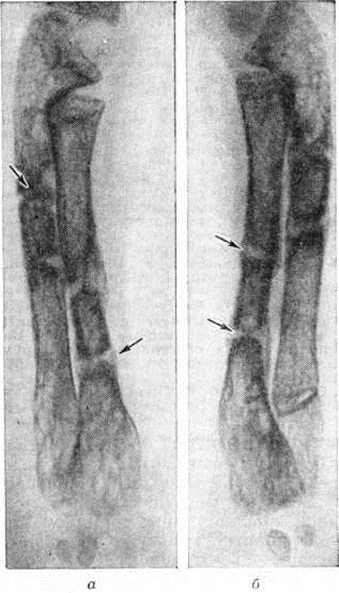

Наиболее часто встречающимся признаком вторичного гиперпаратиреоза при Остеопатия нефрогенная является субпериостальная резорбция (рисунок 1). Она появляется в фалангах и других костях, но фаланги дают более тонкое изображение структуры. Чаще резорбция возникает по радиальной поверхности средних фаланг. Корковый слой костей кажется разволокнённым (рисунок 2). Иногда при Остеопатия нефрогенная можно обнаружить кистозные изменения костей (коричневые опухоли). Субпериостальная резорбция, разволокнение коркового слоя и образование кист, кроме фаланг, наблюдаются в рёбрах, костях таза, ключицах, костях нижней челюсти, бедренных костях, черепе. При Остеопатия нефрогенная своеобразна картина свода черепа, который имеет вид «матового стекла», при более выраженной резорбции изображение костей черепа имеет зернистый вид с более крупными очагами, при этом могут присутствовать участки более плотной кости.

Увеличение количества и толщины костных трабекул при Остеопатия нефрогенная обусловливает рентгенологическую картину остеосклероза. Прежде всего это наблюдается в телах позвонков, где плотные полосы чередуются с более прозрачными. Остеосклероз можно отметить также в рёбрах, черепе и трубчатых костях. Одним из рентгенологических проявлений остеомаляции являются зоны перестройки костной ткани (зоны Лоозера). На снимке они видны как перпендикулярные к корковому слою светлые полосы, напоминающие перелом. Зоны перестройки можно обнаружить в ключице, костях таза (рисунок 3) и длинных трубчатых костях. Остеомаляция может привести к деформации вертлужной впадины. У некоторых больных, долгое время леченных гемодиализом, уменьшается масса костной ткани и появляются переломы. Вторичный гиперпаратиреоз может дать картину фиброзного остеита с очаговым уплотнением кости. Наряду с резорбцией кости происходит образование новой кости. Это наблюдается главным образом у больных, длительно леченных гемодиализом. Периостальное образование новой кости имеет вид тонкой пластинки, отделённой от периоста. У больных после пересадки почки и длительно леченных гемодиализом может наблюдаться остеонекроз (рисунок 4). Степень минерализации костей может быть определена прижизненно методом рентгеноденситометрии (смотри полный свод знаний).